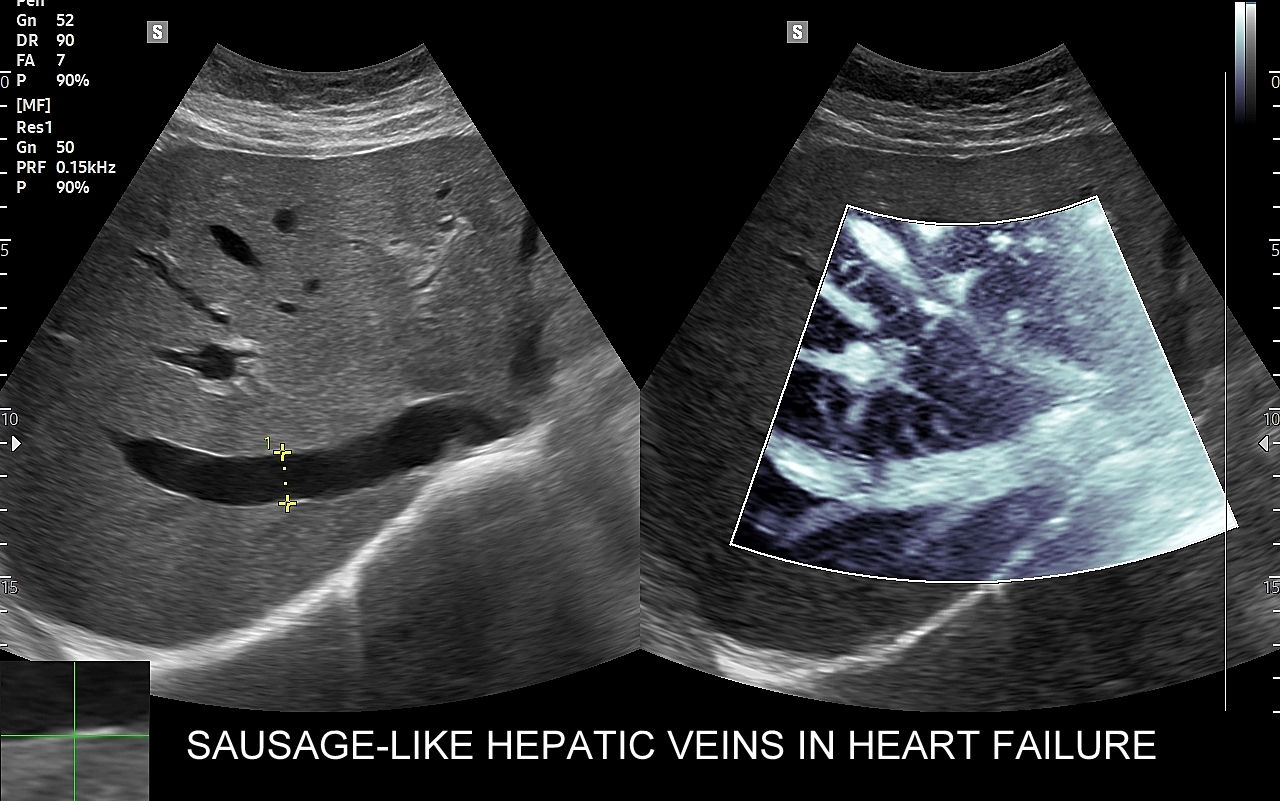

Wątroba posiada unaczynienie różnego typu, a każde o swojej indywidualnej charakterystyce. Są to unaczynienie tętnicze, unaczynienie wrotne (żyła wrotna i jej dopływy z narządów jamy brzusznej), odpływ żylny poprzez żyły wątrobowe. W USG Doppler przepływów wątrobowych bada się każdy z tych układów.

Badanie USG Doppler układu wrotnego wątroby łącznie ze standardową oceną morfologii wątroby i śledziony wykonywane jest najczęściej w ramach diagnostyki nadciśnienia wrotnego, czyli podwyższonego ciśnienia krwi w żyle wrotnej, które może być przyczyną zagrażających życiu żylaków przełyku. Badanie dopplerowskie wątroby uzupełnia również diagnostykę marskości wątroby oraz służy wykrywaniu takich patologii jak zakrzepica w żyle wrotnej i jej dopływach, zakrzepica w żyłach wątrobowych, czy rozprzestrzeniające się nowotwory w naczyniach wątroby.